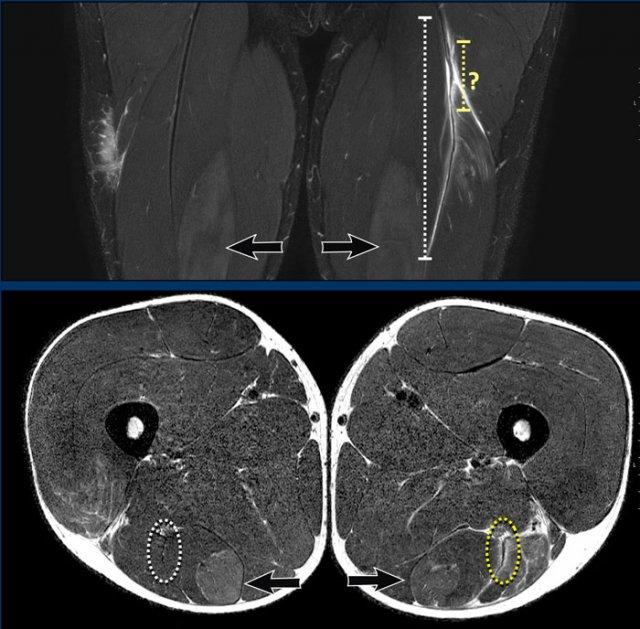

Mặt phẳng coronal so với mặt phẳng axial

Chỉ dựa vào các hình ảnh coronal đơn thuần, đôi khi khó có thể phân loại chính xác mức độ biến dạng. Cần sử dụng các hình ảnh axial để quan sát kỹ hơn.

Trên các hình ảnh axial này, có thể thấy tăng tín hiệu và dày lên của gân cơ nhị đầu đùi bên trái (vòng tròn chấm vàng) khi so sánh với bên không bị tổn thương (vòng tròn chấm trắng).

Trên các hình ảnh này ghi nhận tổn thương toàn bộ chiều dày.

Cả hai viên kem đều rơi trên ảnh axial, cho thấy cả hai gân đều bị bong.

Trên ảnh coronal, tổng mức độ co rút đã được đo và ghi nhận.